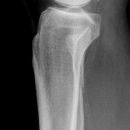

Maisonneuve

Spiralfraktur Tibia